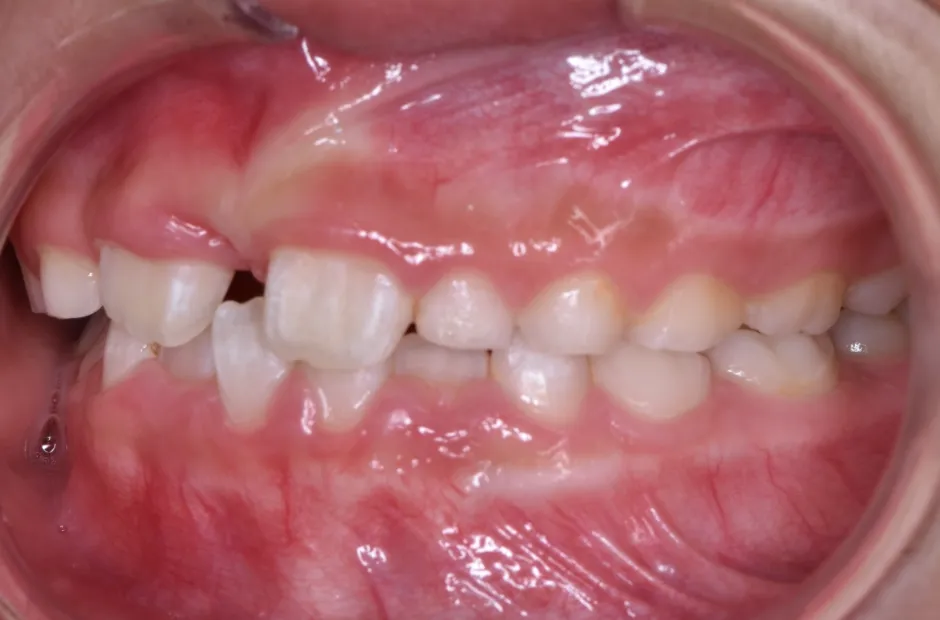

前歯部反対咬合とすきっ歯

| 診断名・主訴 | 前歯部反対咬合とすきっ歯 |

|---|---|

| 年齢・性別 | 7歳・女性 |

| 治療期間・回数 | 1年半、月一回 |

| 治療に用いた主な装置 | 床拡大装置+ブラケット(前歯部) |

| 抜歯部位 | なし |

| 治療費 | 30万円(税抜) |

| リスク・副作用 | 装置による違和感・疼痛・歯肉退縮・歯根吸収・虫歯のリスクなど |

治療前

治療後